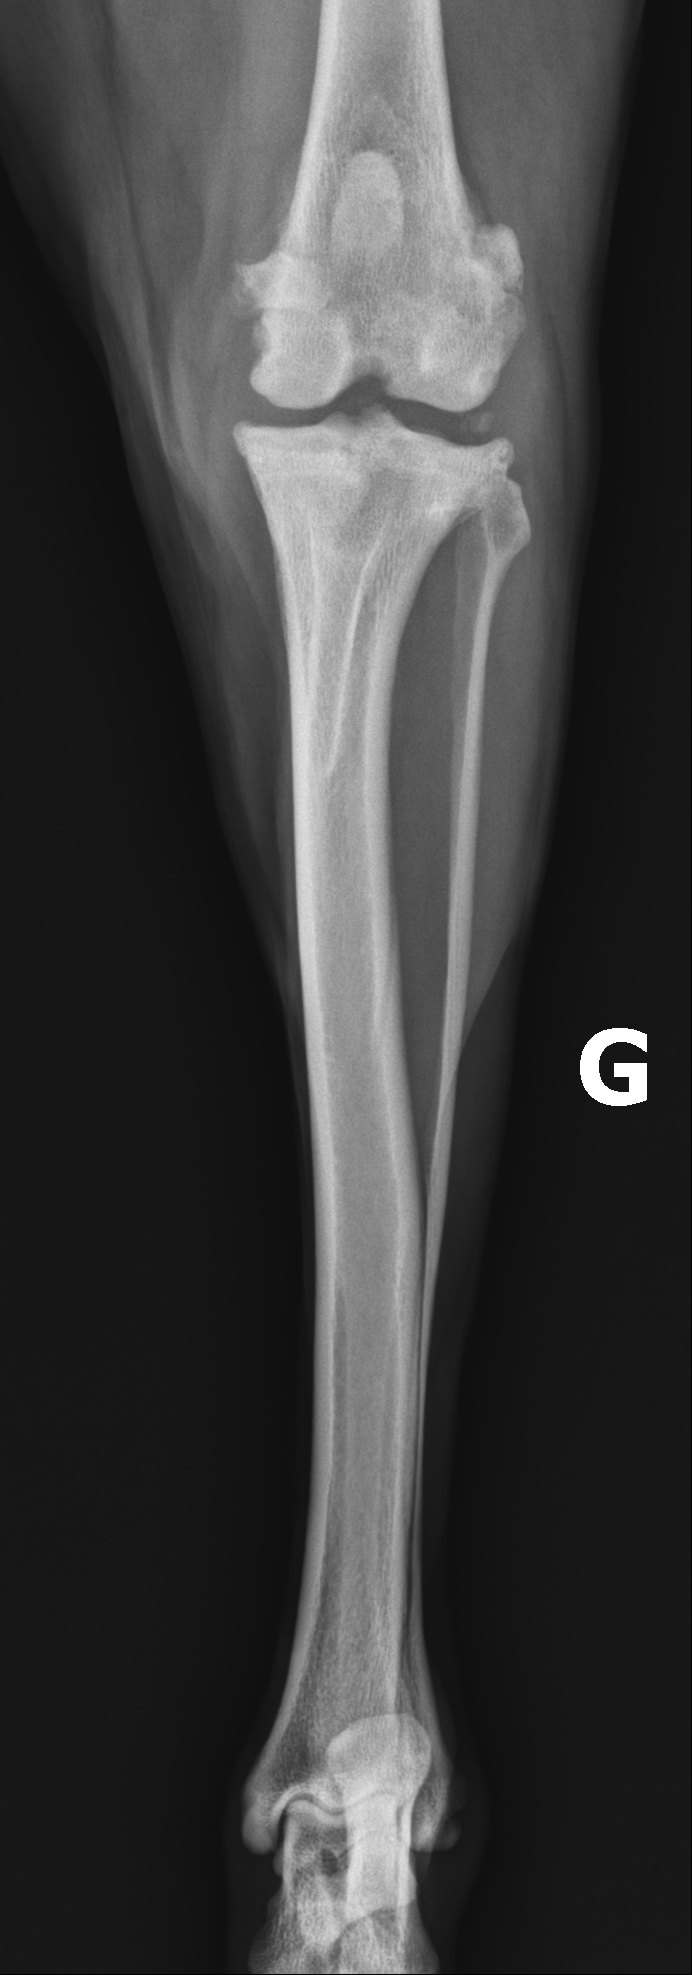

Vue radiographique préopératoire de face du grasset gauche montrant des signes de synovite (en lien avec la rupture du ligament croisé crânial diagnostiquée) et une ostéophytose périarticulaire marquée